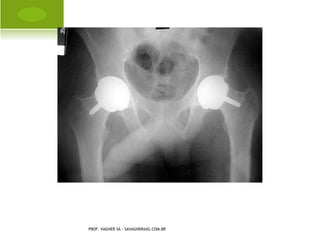

A RTROPLASTIA TOTAL

PROF. VAGNER SÁ - SAVAGNER@IG.COM.BR

A RTROPLASTIA TOTAL PROF.VAGNER SÁ - SAVAGNER@IG.COM.BR

• 174.